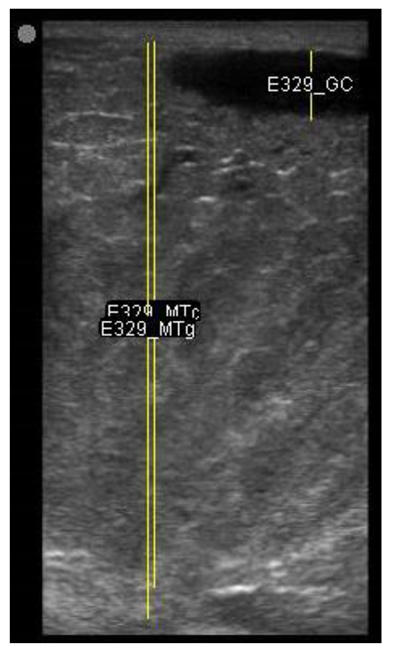

| 107 days of pregnancy (P107) Scanning depth 4.7 cm | ![]() | ![]() | MT generous: 31.7 mm MT conservative: 22.3 mm Gland cistern: 4.5 mm Parenchyma: 8.3 mm Fat Pad: 7.8 mm |